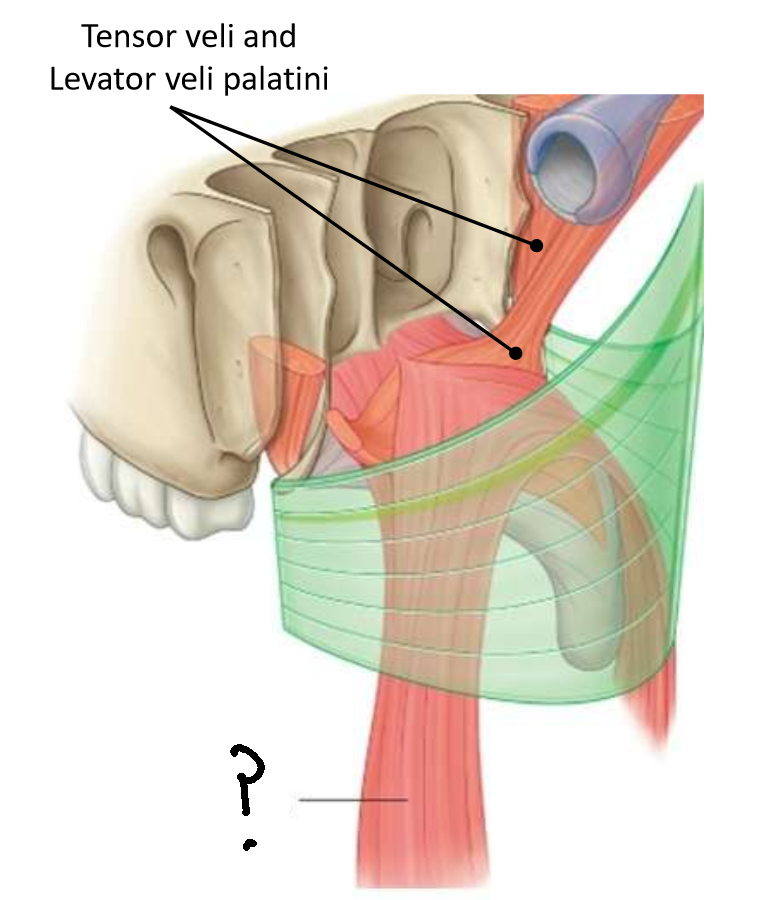

Which muscle is this?

tensor veli palatini

What are the two parts of this muscle?

muscular and fibrous

What is the function of this muscle?

tenses soft palate, opens pharyngotympanic tube

What innervates this muscle?

medial pterygoid nerve of mandibular branch of trigeminal

Which muscle is this?

levator veli palatini

What are the attachments of this muscle?

petrous part of temporal bone and pharyngotympanic tube → palatine aponeurosis

What is the function of this muscle?

lifts soft palate to close nasopharyngeal isthmus

What innervates this muscle?

pharyngeal branch of pharyngeal plexus of vagus nerve

Which muscle is this?

palatopharyngeus

What is the function of this muscle?

elevates the pharynx, depresses the palate to close the oropharyngeal isthmus

What innervates this muscle?

pharyngeal plexus of vagus nerve